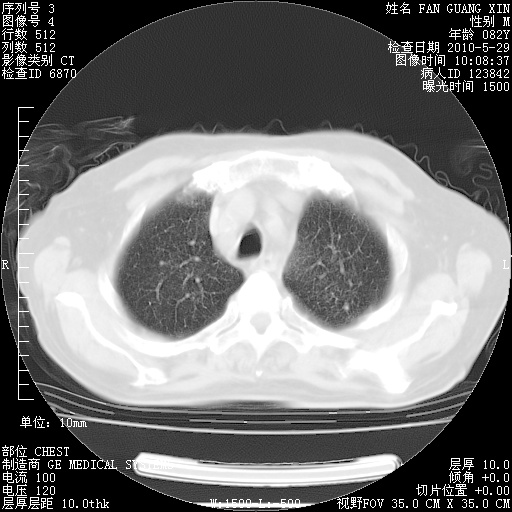

再治疗10天后的肺部CT

阅读此次胸部CT,肺间质渗出性改变较入院时有吸收。目前从体温、白细胞、中性分叶明显增高,肯定存在细菌感染(发生医院感染哦,若无消化道及泌尿系统等感染的依据,肺部感染可能大)。若你院头孢哌酮舒巴坦钠耐药率较高,同意你的方案,若48小时体温仍高,可考虑使用碳青霉稀类抗菌药物,同时可予超声雾化、注意滴数时加大液体量。白蛋白33.30g/L较低哦,需加强营养等支持治疗。